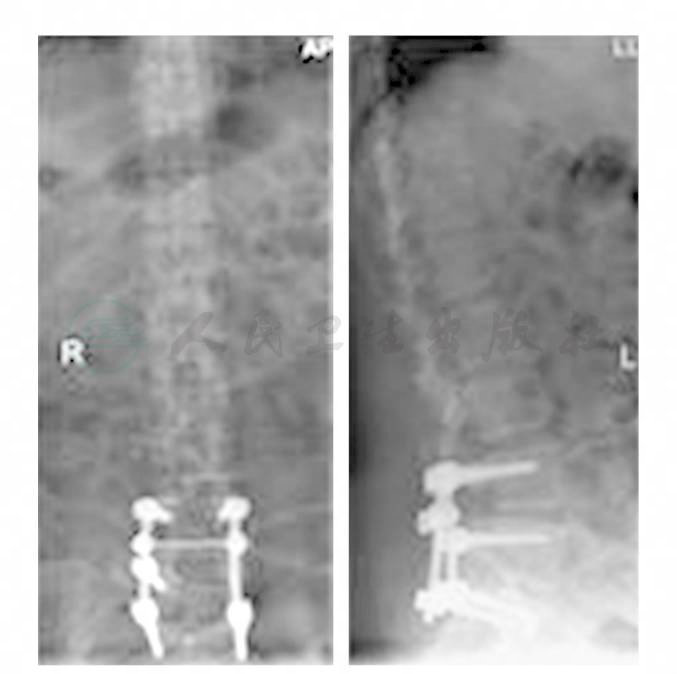

手术后患者的症状基本恢复,手术后两年电话随访,患者可生活自理,无复发的迹象。腰椎X线片无异常(图2)。

图1 全椎板减压,肿瘤切除,椎弓根螺钉内固定术后